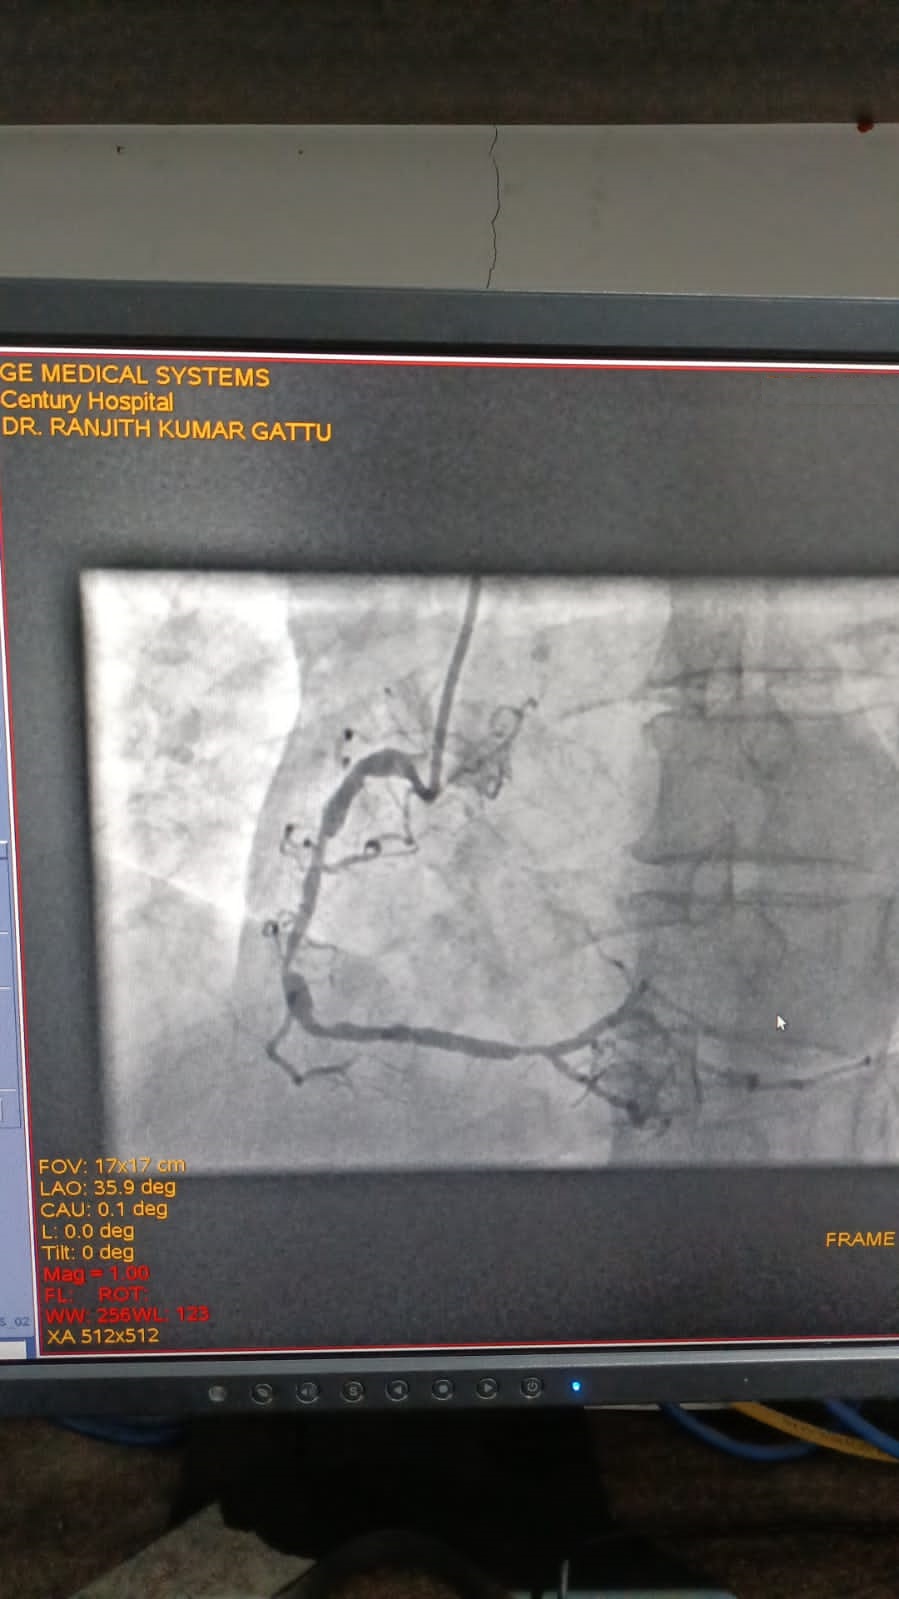

Left Coronary Diseased Artery